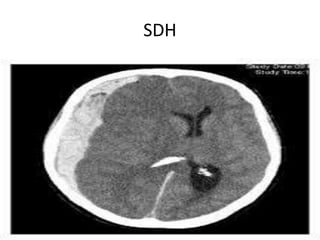

SDH

Trauma • Soft tissueinjuries. • Skull fractures. • Extradural,subdural and subarachniod hemorrhage. • Contusions and diffuse axonal injury with associated cerebral odema.